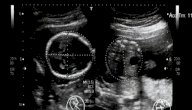

مع بداية الشهر السادس تكونين قد دخلت في نهاية المرحلة الثانية أو الثلث الثاني من الحمل، وتبدأ فترة الحمل في هذا الشهر بالأسبوع الثاني والعشرين الذي يكون أكثر المراحل متعةً وراحة، ولكنه ينتهي في الأسبوع السادس والعشرين، بحيث تكون التغيرات والتطورات تسارعت في الشهر السادس بشكل كبير لكل من الأم والجنين، وسنعرض في هذا المقال تطور وزن الجنين خلال الشهر السادس بالإضافة إلى بعض مراحل نموه.

وزن الجنين خلال الشهر السادس

يمكن بيان وزن الجنين خلال الشهر السادس كما يلي: